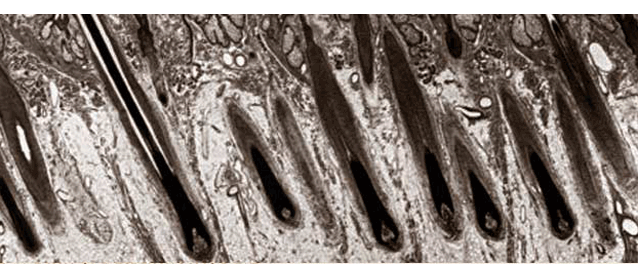

A: Male and female patterned hair loss is secondary to genetics and the hormone Dihydrotesterone (DHT). While hair on the top and front of the head is susceptible to the thinning effects of the DHT hormone, hair on the sides and back of your head isn’t. We use these areas where you have more hair to act as a “hair bank” for those where you don’t.

A: Yes, thanks to a phenomenon called “donor dominance” transplanted hair always grows

as well as it did in its area of origin. The only vulnerabilities are damaged follicles or poor transplantations, and our method virtually eliminates those risks.